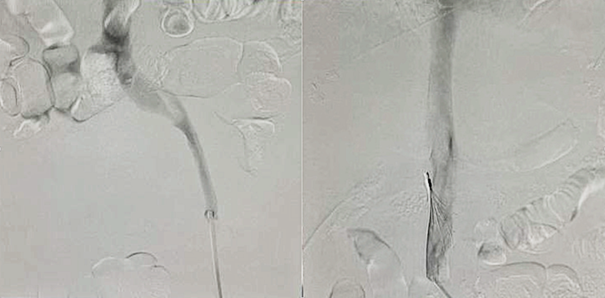

The left photo demonstrates a complete occlusion of the right iliofemoral vein during the intervention. The right photo shows the placement of an inferior vena cava filter.

Initial anticoagulation with rivaroxaban 15 mg twice daily resulted in profuse vaginal hemorrhage. The patient required transfusion of four units of packed red blood cells. Because systemic anticoagulation was temporarily contraindicated, an optional inferior vena cava (IVC) filter (ALN, ALN Implants Chirurgicaux, France) was inserted. Definitive surgical management comprised a total hysterectomy with bilateral salpingo-oophorectomy performed at Hung Vuong Obstetrics and Gynecology Hospital. Postoperatively, anticoagulation was reinitiated with enoxaparin 6,000 IU subcutaneously every 12 h for three days, after which therapy was transitioned to rivaroxaban 15 mg once daily for maintenance.